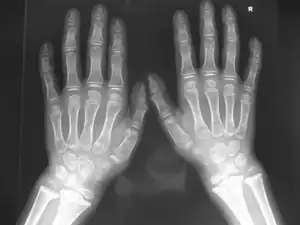

( Marshall-Stickler overlap) Anteroposterior hand radiograph showed, short-stubby hand with large carpal bones associated with pseudoepiphyses of a joint. -